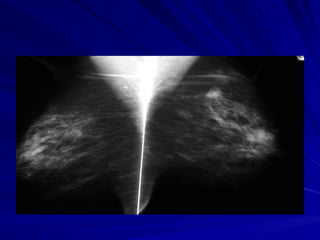

Mamografía normal

Mama normal  superior   Mediolateral  externo  Craneocaudal